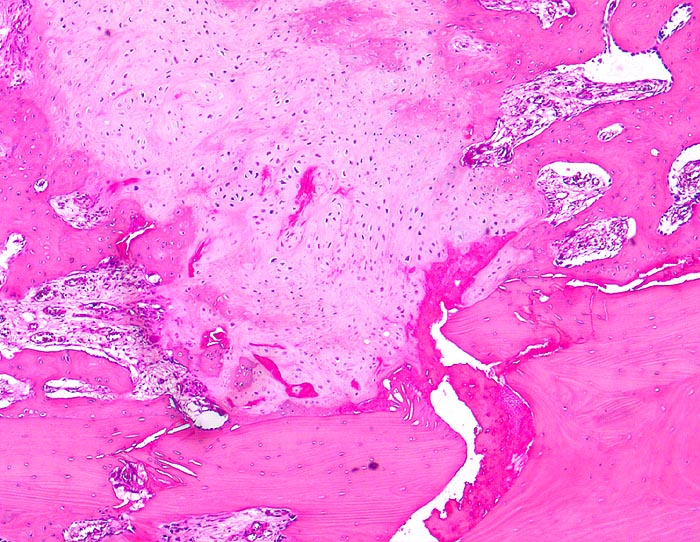

PathoPic – image database / PathoPic ID 4597 - sekundäre Frakturheilung: Frakturspalt

sekundäre Frakturheilung: Frakturspalt

Frakturspalt mit Fibrinablagerungen und neugebildetem, teils mineralisiertem Knorpel. Devitalisierter ortsständiger Knochen mit leeren Osteozytenhöhlen. Markraumfibrose.

Konservativ behandelte Rippenfraktur nach Sturz vor einem Monat.

Der Nachweis von neugebildetem Knorpel entlang der Frakturlinie im Innern des Knochens ist ein Charakteristikum vor allem der Rippenfraktur als Folge einer mangelhaften Ruhigstellung. Die notwendige Resorption des avitalen Knochens führt zu einer Heilungsverzögerung.

160